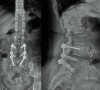

Results: Following leg pain recurrence, a hybrid L4-S1 fusion was performed. After surgery, there was clinical improvement and six months later, the patient returned to daily activities. The radiological study after five-year follow-up shows adequate implant position, without signs of loosening, compatible with solid fusion.